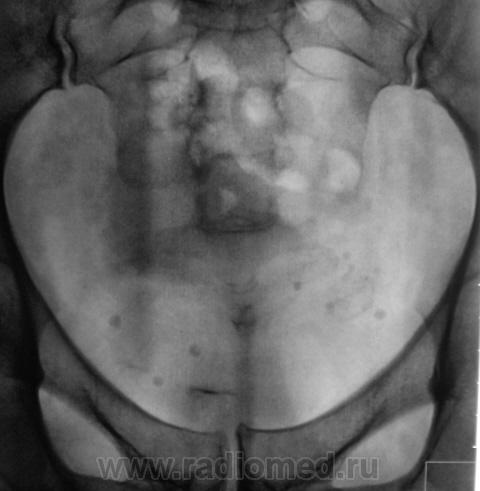

Пациент с клиникой правосторонней почечной колики направлен на рентгенологическое исследование.

В проекции среднего сегмента правой почки тень конкремента. Отсутствие признаков расширения собрательной системы правой почки.

Во-Во! И тени флеболитов в проекции малого таза.